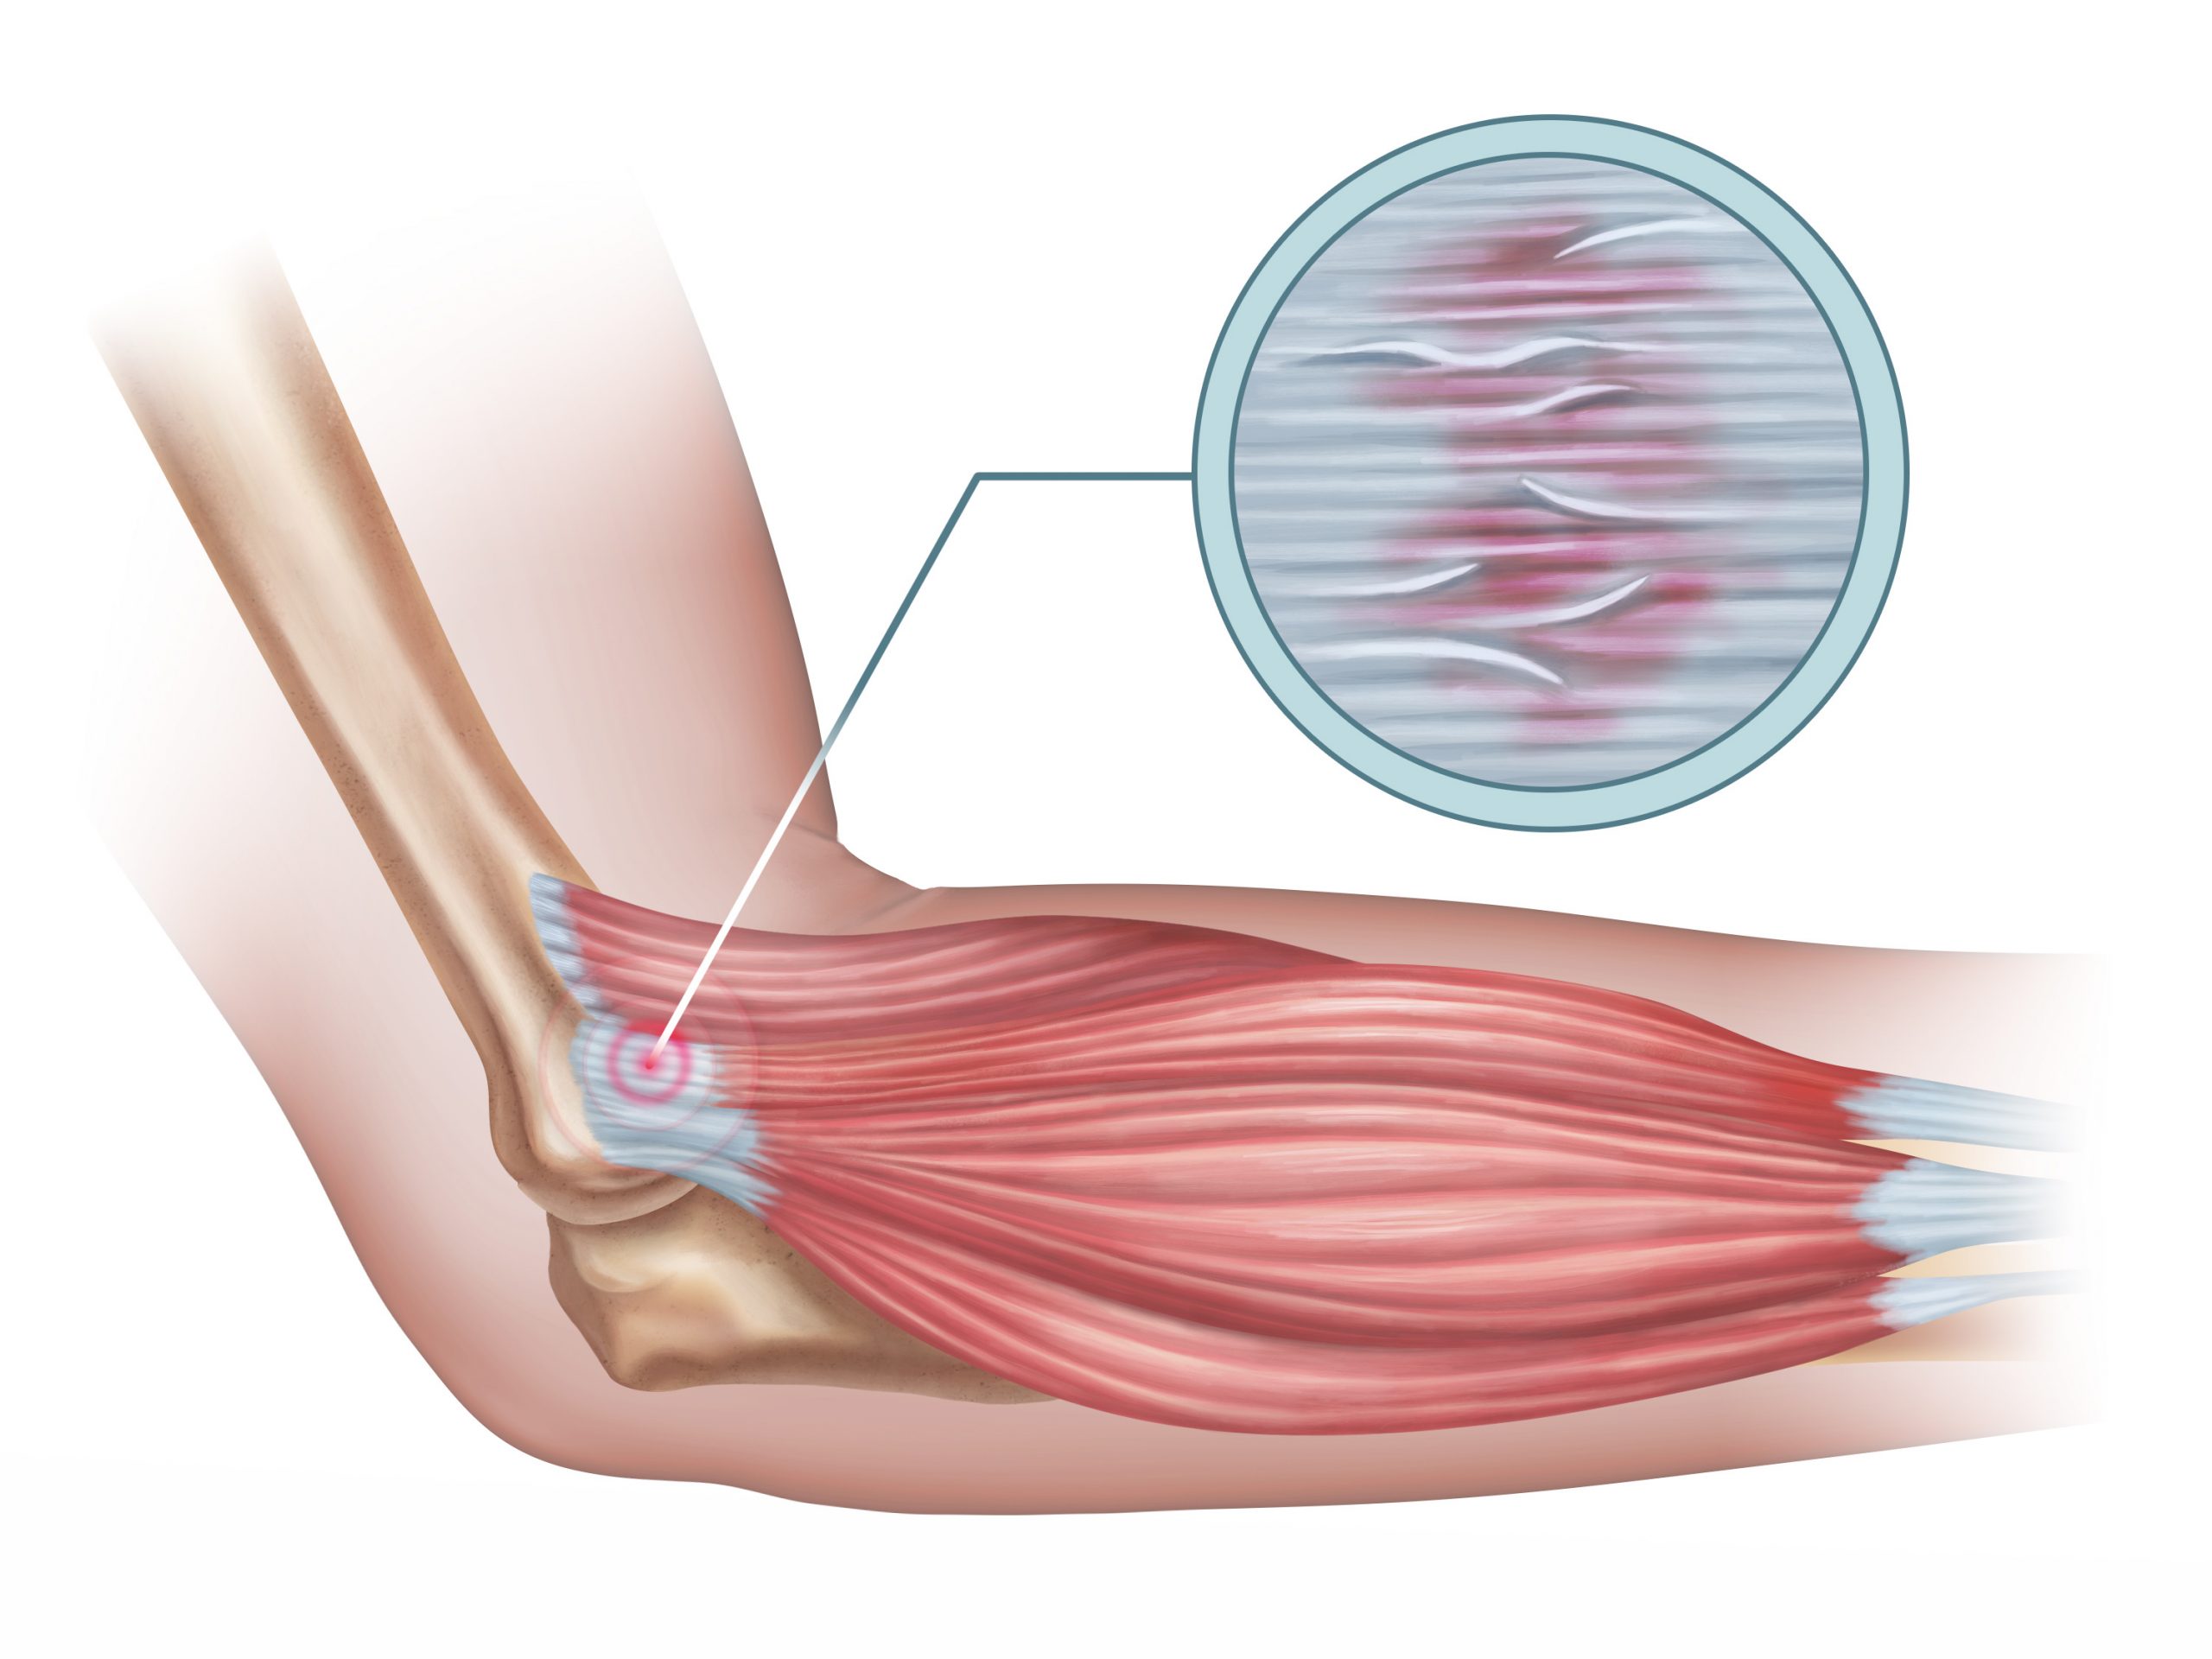

Why does Tennis Elbow occur?

Known as an overuse injury, Tennis Elbow is a tendonosis, not a tendonitis. So what does that mean? Well a tendonosis occurs over time and leads to degenerat…